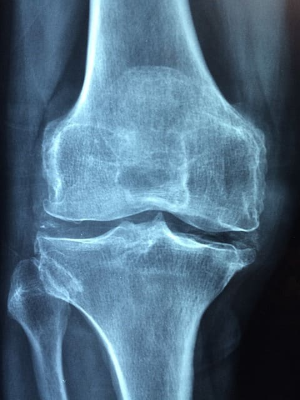

전신성 홍반성 루푸스는 면역계을 공격하여 다른 조직에도 염증과 손상을 일으켜 합병증을 일으키기도 합니다. 추울 때는 혈액 응고를 통해 손가락이나 발가락이 하얗거나 파래지는 레이노 현상이 발생하기도 합니다. 또한 대표적인 합병증에는 치료약 중 하나인 스테로이드의 장기복용에 따른 골다공증이 발생하기도 합니다. 그 외 신장염, 신장염, 뇌졸중을 일으킬 수 있고, 관절 기형이나 임신 합병증, 심장 마비와 같은 무서운 병도 초래하기도 합니다.